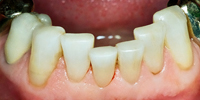

Die Abb. 1 bis 4 sollen als anschauliche Beispiele für gesunde und kranke Fundamente dienen.

Ein 31 Jahre alter Patient zeigt einen starke Zahnfleisch-Rückgang im Oberkiefer (Abb. 1 und 3) und wir beschliessen, diese Rezessionen zu behandeln.

Der Erfolg der Behandlung ist deutlich in den Abb. 2 und 4 zu sehen. Sehr augenfällig konnte die Situation um den Eckzahn im linken Oberkiefer verbessert werden (vergleiche dazu Abb. 3 vorher und Abb. 4 nachher).